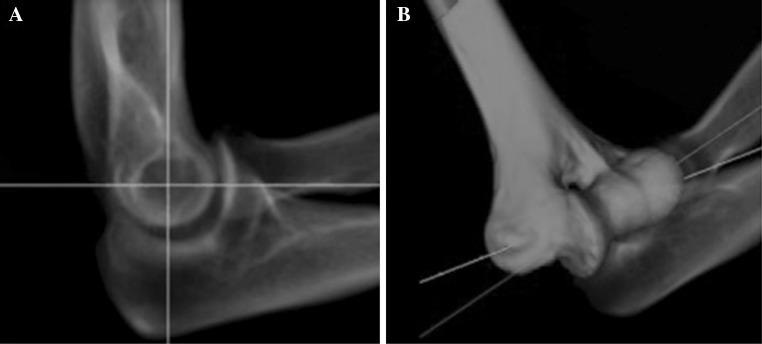

External fixation of the elbow requires identification of the elbow rotation axis, but the accuracy of traditional landmarks (capitellum and trochlea) on fluoroscopy is limited. The relative distance (RD) of the humerus may be helpful as additional landmark. The first aim of this study was to determine the optimal RD that corresponds to an on-axis lateral image of the elbow. The second aim was to assess whether the use of the optimal RD improves the surgical accuracy to identify the elbow rotation axis on fluoroscopy. CT scans of elbows from five volunteers were used to simulate fluoroscopy; the actual rotation axis was calculated with CT-based flexion-extension analysis. First, three observers measured the optimal RD on simulated fluoroscopy. The RD is defined as the distance between the dorsal part of the humerus and the projection of the posteromedial cortex of the distal humerus, divided by the anteroposterior diameter of the humerus. Second, eight trauma surgeons assessed the elbow rotation axis on simulated fluoroscopy. In a preteaching session, surgeons used traditional landmarks. The surgeons were then instructed how to use the optimal RD as additional landmark in a postteaching session. The deviation from the actual rotation axis was expressed as rotational and translational error (±SD). Measurement of the RD was robust and easily reproducible; the optimal RD was 45%. The surgeons identified the elbow rotation axis with a mean rotational error decreasing from 7.6° ± 3.4° to 6.7° ± 3.3° after teaching how to use the RD. The mean translational error decreased from 4.2 ± 2.0 to 3.7 ± 2.0 mm after teaching. The humeral RD as additional landmark yielded small but relevant improvements. Although fluoroscopy-based external fixator alignment to the elbow remains prone to error, it is recommended to use the RD as additional landmark.

摘要